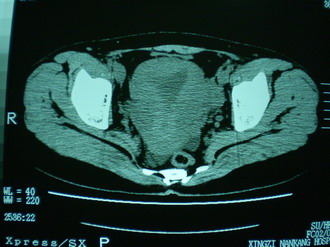

子宫增大,内可见类三角形低密度区,子宫后方可见类圆形团块状影,内部密度不均匀,可见靶样结构,结合病史考虑1子宫后方宫外孕(宫内假孕囊形成)2子宫肌瘤合并妊娠

子宫明显前倾,增大,宫颈增大呈分叶状。子宫直肠窝见不规则形水样低密度。(膀胱胀尿不理想)

考虑:1、宫颈部占位;

2、子宫直肠窝少量积液(盆腔炎所致)。

考虑:1、宫颈部占位(宫颈癌?);

2、子宫直肠窝少量积液。

1、前曲子宫,2、宫颈部占位?3、盆腔及右输卵管积液?宫内积血?4、左侧卵巢囊肿。